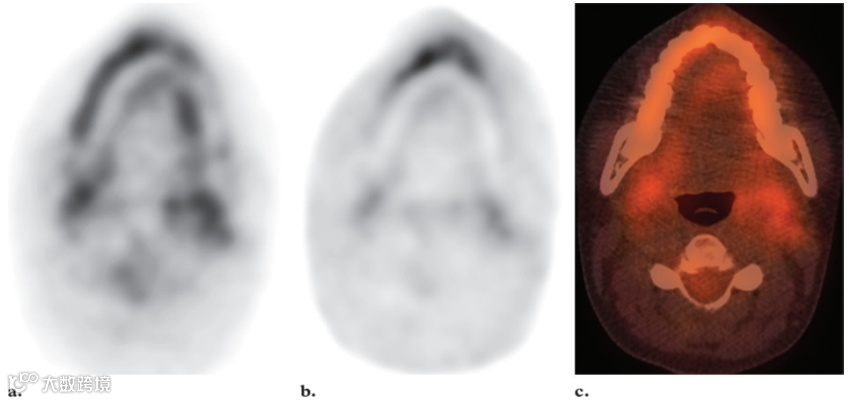

最强烈的FDG活性存在于正常的大脑皮层和基底神经节中,因为大脑依赖糖酵解代谢作为能量来源(图1)。大脑代谢可能占整个空腹状态下的身体代谢的20%。大脑的总吸收量约为注射剂量的FDG的6%。由于韦氏环淋巴组织的生理活动,腺样体、扁桃体和舌根通常会出现轻度至中度的摄取。然而,在韦氏环中可以看到明显的强烈摄取(图2),尤其是在儿童中,因为这些淋巴组织的生理活性很高,在6-8岁达到峰值,此后逐渐减弱。在儿童体内这些区域的正常FDG摄取并不一定意味着有疾病。通常情况下,生理性扁桃体和腺样体摄取的对称模式有助于识别这种正常变化。软腭也可显示强烈的放射性示踪剂摄取。唾液腺的摄取情况各不相同,但通常为轻度至中度(图3)。有研究报告称,约51%的患者腮腺有轻度至中度摄取,腮腺高度摄取约14%。颌下腺和舌下腺的摄取情况各不相同,阳性率分别为53%和72%。化疗或放射治疗后也可见唾液腺摄取量弥漫性增加。由于近期手术或放射治疗后出现急性炎症,唾液腺对FDG的摄取可能不对称。然而,放射治疗最终可能导致患侧摄取减少。

图2. 最大强度投影 (MIP) FDG PET 图像 (a) 和横向FDG PET (b)、CT (c) 和融合PET/CT (d) 图像显示正常扁桃体中有明显且对称的摄取 (箭头) 以及腮腺中有双侧轻度摄取 (b-d中的箭头) 。